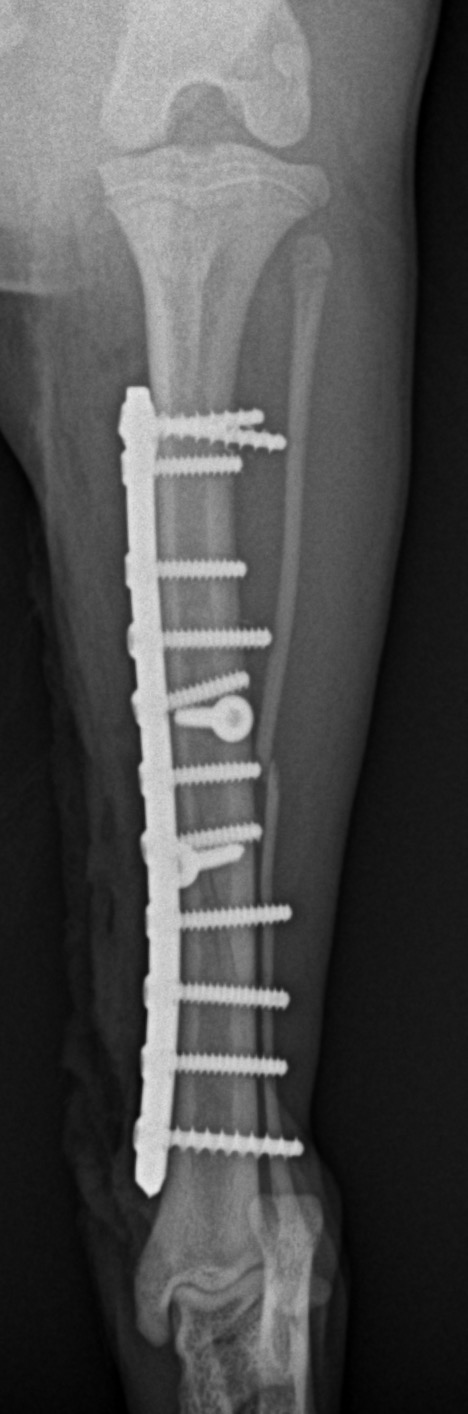

脛骨中央部らせん状骨折 階段で転んだワンチャンが、骨折をしてしまったので手術をしてほしいとの連絡があり対応しました。比較的、長い範囲でのらせん状骨折です。2本のポジションスクリューとプレーティングにより骨接合術を行いました。 症例カテゴリー 放射線治療整形外科軟部組織外科脳神経外科内科腫瘍外科救急・集中治療リハビリテーション科腫瘍内科内視鏡科脳神経科呼吸器外科中医・漢方猫の腎移植循環器科